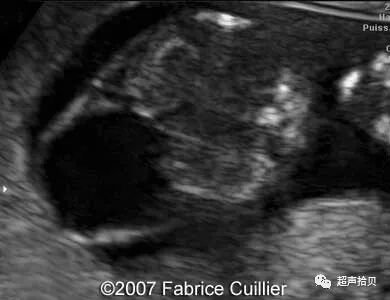

图1:横向声像图显示位于中线蛛网膜囊肿(C), 彩色多普勒没有血流显示;